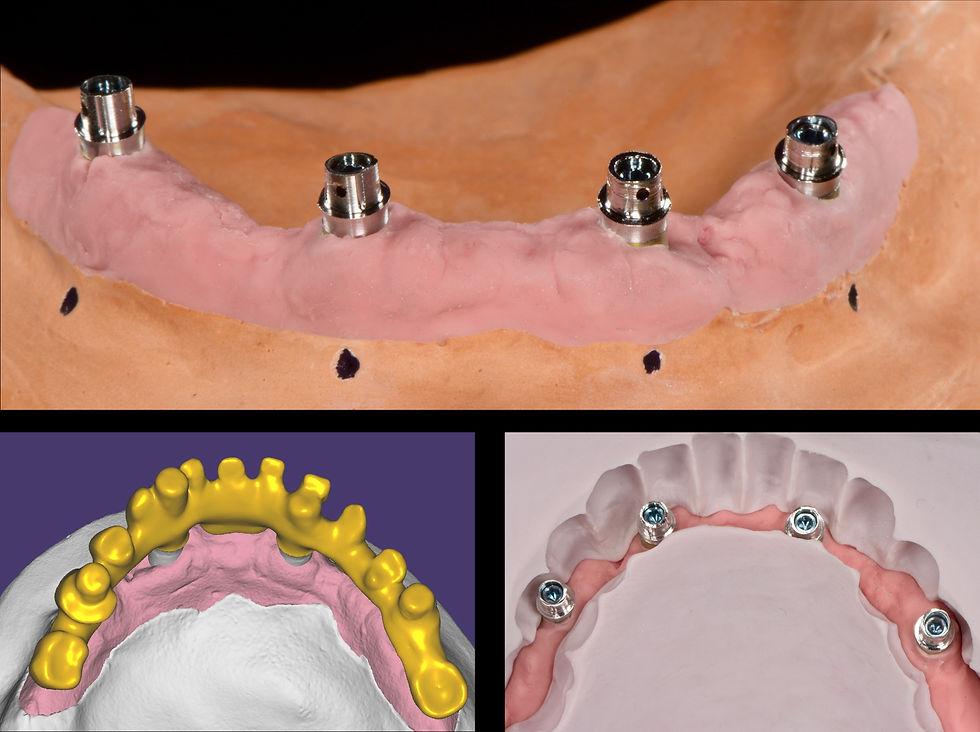

Cobalt chrome bases used for lab scanning.

Milled structure in cobalt chrome soldered to the preformed bases using a voltaic arc

Relationship between the lower Toronto Bridge and the neck of Prama Long Neck implants